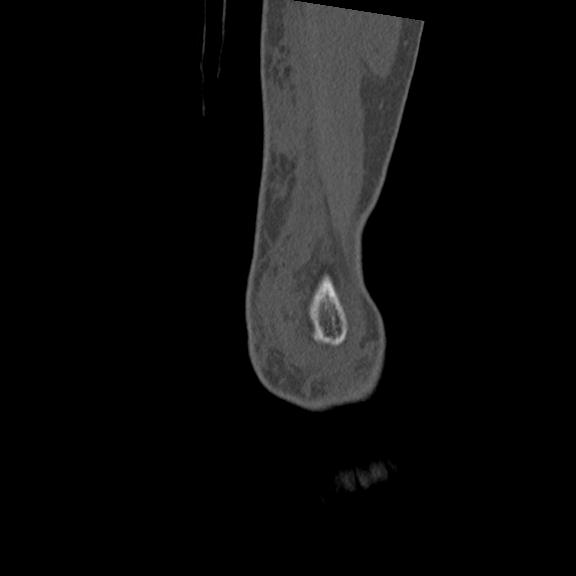

56476 8/28 4R 1/21 2R 左足関節 デジカメ写真 72歳女性 右足関節AS